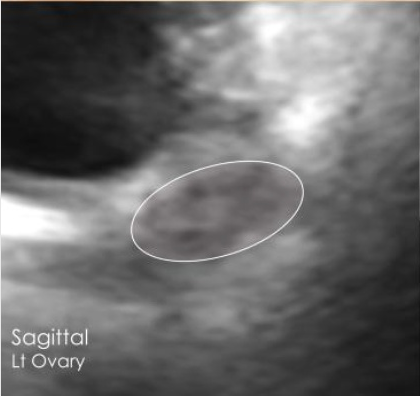

Left ovary transverse view ultrasound Left ovary sagittal view ultrasound

Bilateral Ovaries

12 antral follicles — within normal range

Normal

Both ovaries are a healthy size and shape. A total of 12 antral follicles were visible (5 on the right, 7 on the left), which is within the normal range for your reproductive health. This is a reassuring result.

Note: These images were captured at home by a user with no medical training using Chealth technology, demonstrating the quality achievable with our guided scanning system.